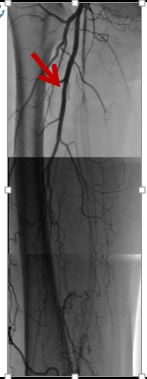

1684. На представленной ангиографии отмечена